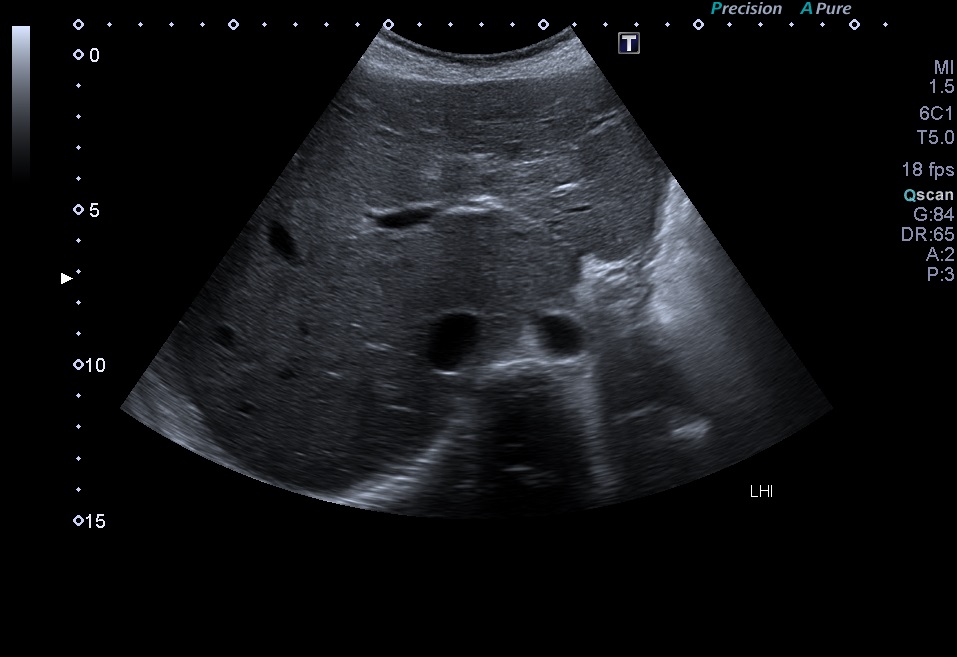

En la última revisión se realiza una ecografía abdominal, donde se observa un hígado de tamaño conservado y ecogenicidad heterogénea con áreas parcheadas hiperecogénicas (Fig. 1), ausencia de lesiones focales, y flujos vasculares sin alteraciones. En la elastografía se registraron valores aumentados, de hasta 20 kPa (Fig. 2). Se inició un programa de seguimiento periódico por parte de la sección de gastroenterología, con realización de ecografías-elastografías seriadas, cada seis meses.